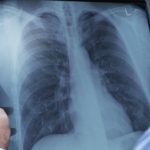

Integrated data vital in stopping spread of TB: U of M study

December 10, 2018 —

Stopping TB depends on the availability of high-quality, comprehensive data to ensure early treatment, according to new study